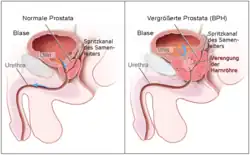

Benign prostatic hyperplasia

In benign prostatic hyperplasia (BPH), men experience urinary obstruction and are unable to urinate, thus leading to urinary retention.[2] α1 specific blockers have been used to relax the smooth muscle in the bladder and enlarged prostate.[25] Prazosin, doxazosin, and terazosin have been particularly useful for patients with BPH, especially in patients with hypertension.[2] In such patients, these drugs can treat both conditions at the same time.[2] In patients without hypertension, tamsulosin can be used, as it has the ability to relax the bladder and prostate smooth muscle without causing major changes in blood pressure.[25]